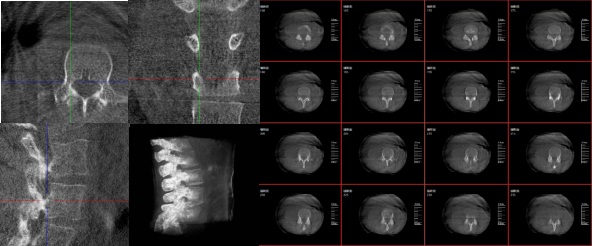

6.可视化:将生成的三维模型以可视化的方式展示给医生,帮助他们更好地理解患者的病情。

3.手术导航:在手术过程中,医生可以通过三维重建技术实时观察手术器械的位置,提高手术的精确性和安全性。例如在关节外科手术中,存在植入物的错位在术中不易发现的情况,如果在术后CT中检查出,就不可避免地需要翻修手术,这就会增加并发症的概率以及感染风险。而通过术中三维影像设备PLX C7600的检查,可以立即发现植入物的错位,减少不必要的第二次手术。